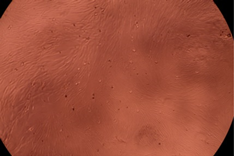

| Sample | Micrographs | ||

|---|---|---|---|

| 24 h | 48 h | ||

| Control |  |  | |

| F127 | 10 µg/mL |  |  |

| 50 µg/mL |  |  | |

| 100 µg/mL |  |  | |

| 200 µg/mL |  |  | |

| F127/PA = 10/1 (g/g) | 10 µg/mL |  |  |

| 50 µg/mL |  |  | |

| 100 µg/mL |  |  | |

| 200 µg/mL |  |  | |